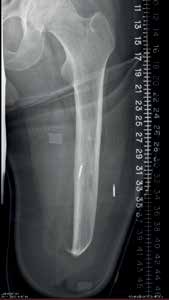

Zwei Beinamputierte wurden für eine IMES-Studie ausgewählt: ein Oberschenkelamputierter (TF = transfemoral) und ein Unterschenkelamputierter (TT = transtibial). Bei beiden Amputierten handelte es sich um erfahrene Anwender mit dem Aktivitätsgrad K3. Feine Drahtelektroden wurden verwendet, um zu überprüfen, dass von jedem Muskel bei einer willkürlich ausgelösten Kontraktion ein ausreichendes myoelektrisches Signal erfasst werden konnte. Zwei IMES-Sensoren wurden anschließend bei beiden Anwendern implantiert, beim oberschenkelamputierten Probanden in den Musculus biceps femoris und den Musculus vastus lateralis und beim unterschenkelamputierten Probanden in den Musculus tibialis anterior und den Musculus gastrocnemius. Jeder Eingriff dauerte etwa 30 Minuten und wurde unter lokaler Anästhesie und leichter Sedierung durchgeführt (Abb. 1). Beide Probanden wurden darum gebeten, bis zwei Wochen nach der Operation Unterarmgehstützen anstelle ihrer Prothesen zu verwenden, und es wurde ihnen eine vierwöchige Rehabilitationszeit gewährt, bevor mit den IMES-Tests begonnen wurde.

Jeder Sensor hat einen Durchmesser von etwa 2,5 mm und eine Länge von 16 mm, wobei die kundenspezifische Elektronik in einem Keramikzylinder untergebracht ist. Jedes Zylinderende ist aus leitfähigem Metall hergestellt, das als Elektrode dient (Abb. 2). Nach der Implantation wurden Röntgenbilder aufgenommen, um zu bestätigen, dass das Implantat an der richtigen Stelle sitzt, entsprechend der beabsichtigten Platzierung des Schafts (Abb. 3). Nachdem die Sensoren in die verbleibenden Muskeln des Stumpfes implantiert wurden, kann der im Prothesenschaft untergebrachte Spiral-Empfänger dazu verwendet werden, drahtlos über ein magnetisches Feld Energie und Informationen an die IMES zu übermitteln und von diesen zu empfangen. Der Spiraldraht-Empfänger wird mittels eines Spulentreibers gesteuert, der das magnetische Feld reguliert. Die IMES-Steuerschnittstelle versorgt den IMES mit Energie, sorgt für die Programmierung, empfängt Daten vom IMES und ist mit dem Message Broker für das bionische Signal (BSMB = „bionic signal message broker“) verbunden, der das IMES-System und die Prothesen von Össur miteinander verbindet (Abb. 4). Die IMES sind aufgrund von Stabilitätsproblemen nur in der Lage, gefilterte, gleichgerichtete und integrierte Signale zu versenden, und die Abtastrate des Sensors betrug 236 Abtastwerte pro Sekunde.